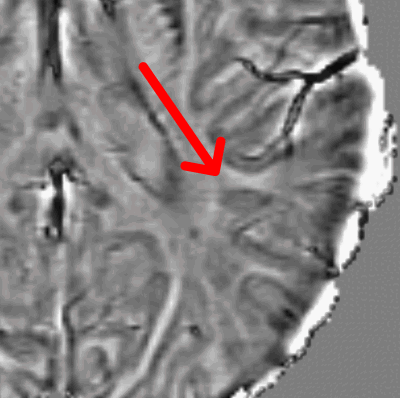

Paramagnetic (Iron) Rim Lesions

Multiple Sclerosis (MS) is characterized by the accumulation of areas of inflammatory injury ("lesions") to the brain and spinal cord. In the aftermath of a new lesion formation, the brain and immune system attempt to heal. In some cases — for reasons yet unknown — a lesion will fail to repair and instead develop ongoing, low-grade inflammation. In these types of "chronic active lesions", cells at the border (rim) of the lesion will often sequester iron, a paramagnetic molecule that can be readily visualized using special MRI sequences. These iron-laden cells tend to be highly inflammatory. They can be visualized as a dark border around a typical MS lesion. Many questions surround the role of these lesions in MS: what is the natural history of these lesions? Do they predict certain clinical outcomes? Can they be treated by any of our current therapies? We have recently shown that these lesions are highly specific for a diagnosis of MS. We collaborate closely with Daniel Reich at the NIH Translational Neuroradiology Section as well as with Sathish Dundamadappa at UMass Radiology and Alex Rauscher at University British Columbia.